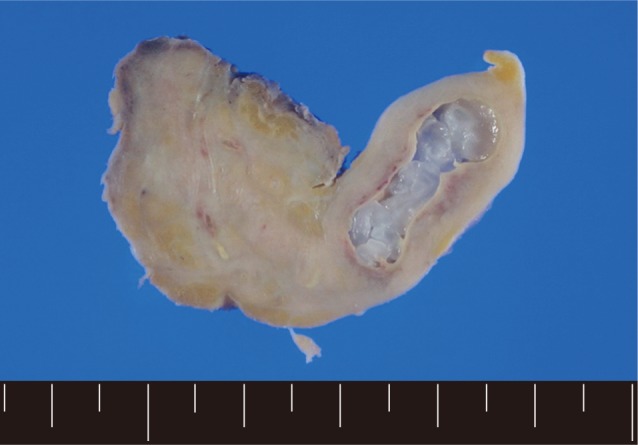

A 56-year old male visited our out-patient clinic for pancytopenia. Bone marrow biopsy and karyotype analysis showed myelodysplastic feature with 14% blast count and normal karyotype, indicating MDS, refractory anemia with excessive blast. He received 4 cycles of decitabine treatment during searching for matched unrelated donor, and partial response was shown. Allogeneic peripheral HSCT with myeloablative conditioning regimen consisting of busulphan and cyclophosphamide was performed from a HLA full-matched unrelated donor. However, at day 5 post-HSCT, 5 cm-sized hard and movable mass in the left scrotum and multiple palpable lymph nodes was detected at the left inguinal area. Pelvic magnetic resonance imaging and computed tomography were done and it was suspected initially as a myeloid sarcoma in the subcutaneous fat layer of the left scrotum and pathologic lymphadenopathy at the left inguinal area (Fig. 1). In order to confirm the diagnosis, gun biopsy was done on the left scrotal mass to avoid bleeding due to thrombocytopenia after HSCT. The result of the gun biopsy was inflamation of fibrovascular soft tissues with extensive interstitial eosinophilic infiltrations without evidence of malignancy. Persistent peripheral eosinophilia was also developed after HSCT. Subsequently, IgG antibody tests for paragonimiasis, cysticercosis, sparganosis, and clonorchiasis were done, and the results were positive for sparganosis and negative for all others. We re-evaluated the patient's past history and found out that he had swam in the river and ate raw fish, cow liver, and pork meat frequently when he was young. For a next step, excision biopsy was done as an approach for therapeutic diagnosis after recovery of thrombocytopenia. The cut surface of the biopsied specimen showed a cyst filled with whitish and myxoid tissues, measuring 2.0×0.6 cm (Fig. 2). The biopsy result was severe acute and chronic inflammation and fibrosis with a sparganum worm (Fig. 3). He was discharged after complete wound healing and stabilization of the post-HSCT condition.

(A) Pelvic magnetic resonance imaging which shows a peripherally enhanced tubular lesion in T1-weighted image at a left subcutaneous fat layer of the left scrotum. (B) Pelvic computed tomography which shows an irregular-shaped enhanced soft tissue density lesion with peripheral infiltrations at a left subcutaneous fat layer of the left scrotum.